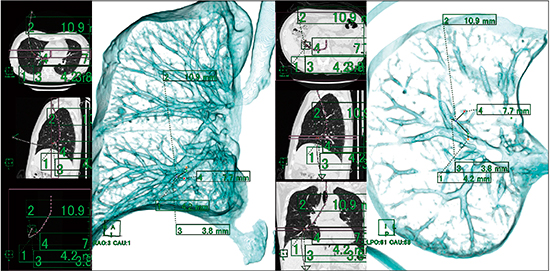

(2) 二次元画像上で各点の距離を計測する(図4)。

図4 画像処理:各点の距離の測定

(3) 三次元画像上に点と距離が反映されるので,この点を頼りに口側から病変部までの経路を動画保存する(図5)。これで病変部への経路と位置をナビゲーションできる。

図5 画像処理:仮想気管支内視鏡画像によるナビゲーション画像

(4) 内側からの情報のみでは術中に位置関係が把握できないことも予想されるため,外側の情報としての三次元画像も作成した(図6)。これは,仮想内視鏡画像作成用のアプリケーションをそのまま利用し,視点を体外に設定して画像のオパシティを変更することで作成できる。

図6 画像処理:外側から見た位置関係